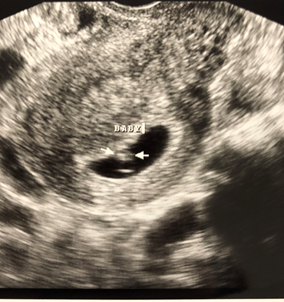

Not too much to see but there's a little baby there with a heartbeat of 122 BPM

The two black dots to the right are the hematoma bleeds😥 Pic was taken far away like this because they are more focused on the SCH.

Since I am very high risk i will be getting weekly ultrasounds to watch the bleed. Praying next week the baby will have grown and the hematoma will be smaller. Keeping faith.